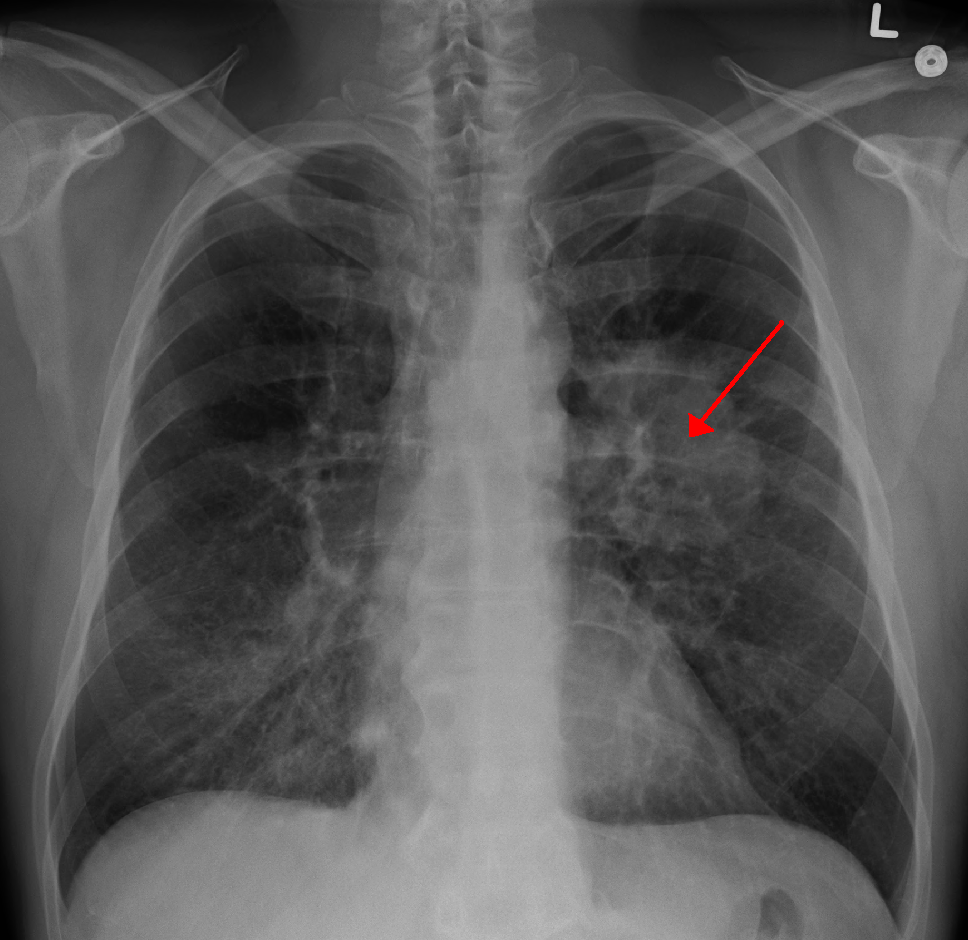

Szilasi Mária, a társaság alelnöke, a Debreceni egyetem (DE) tüdőgyógyászati klinikájának igazgatója kiemelte: napjainkban a férfiak és a nők tüdőrák-halálozási statisztikáját Európán belül Magyarország vezeti. A betegség elődleges rizikófaktora a dohányzás: hazánkban a felnőtt lakosság harmada cigarettázik rendszeresen, míg a daganatosok mintegy kilencven százaléka gyújt rá napi szinten.

A professzor a másik legjelentősebb tüdőgyógyászati betegségként a népbetegségnek számító COPD-t, a krónikus obstruktív tüdőbetegséget említette. A betegek száma évente 15 ezerrel emelkedik, összességében a megbetegedés csaknem félmillió embert érint hazánkban.